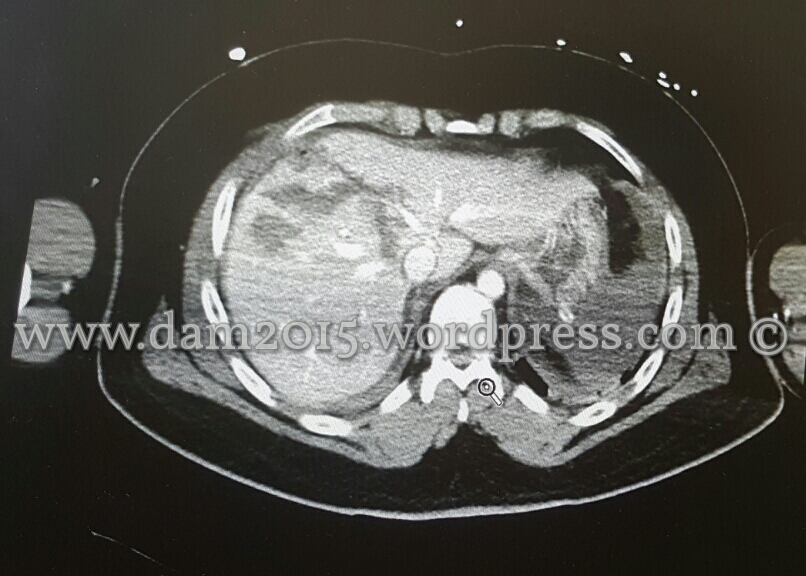

Paziente uomo, 46 anni.

Politrauma per incidente stradale.

Alla TC si rileva lesione epatica ramificata coinvolgente i segmenti VII e VIII e che si approfonda verso l’ilo, sino alla Vena Cava (che mostra comunque normale opacizzazione e calibro), a livello della confluenza delle sovraepatiche.

Lesione di IV grado secondo la “Liver Injury Scale” (1994 revision)